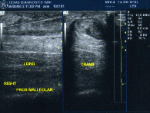

Achilles Tendon: long axis correlation to transverse view must be obtained.